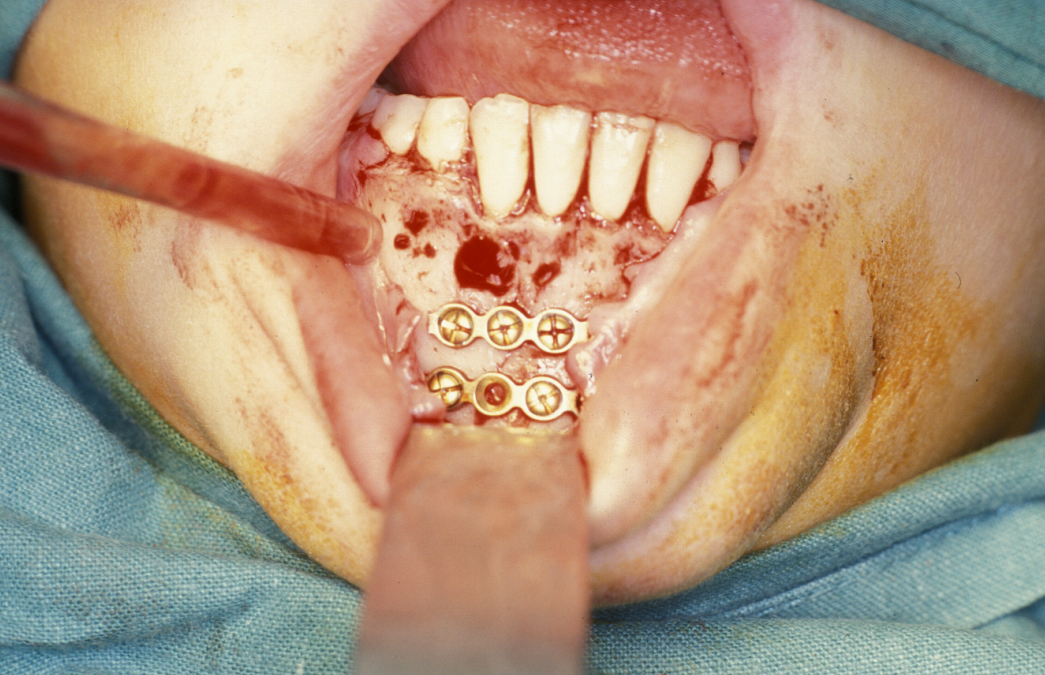

Fixation is undertaken with titanium mandibular plates. According to Champy’s principles, in the mandibular symphyseal and parasymphyseal (the middle region of the mandible) region two mandibular plates are required, one just below the level of incisor/premolar apices and above the mental foramen and one as low down on the buccal surface as possible parallel to the lower border of the mandible. This is shown in Figure 4.